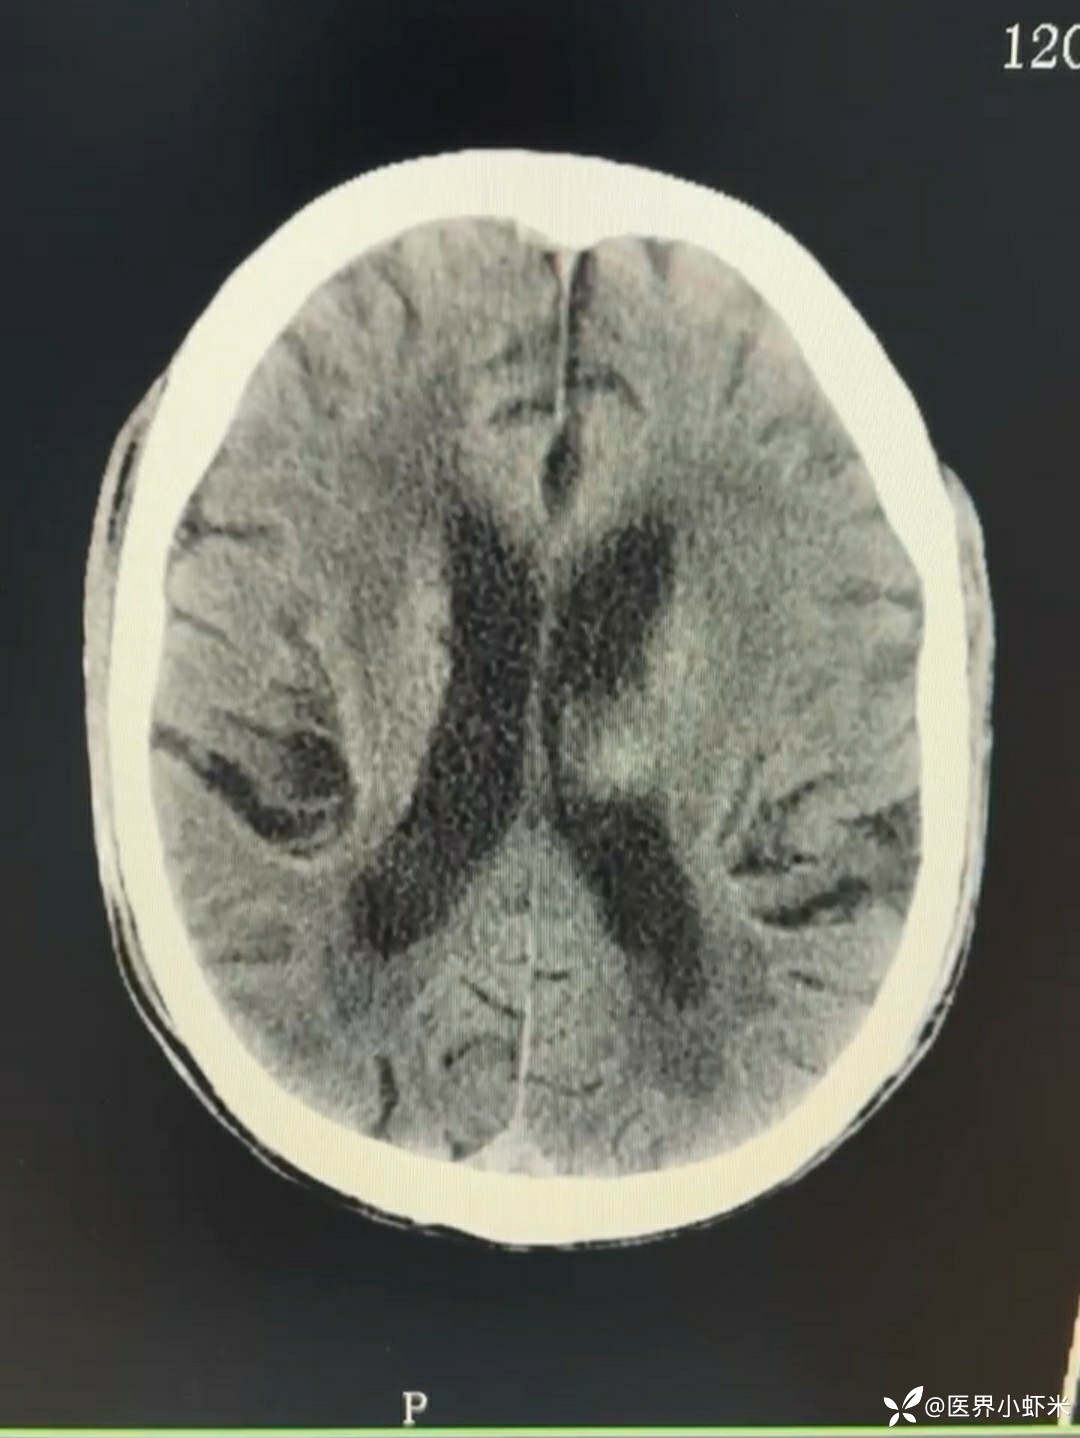

目前考虑:1.中央型肺癌伴2.肝继发恶性肿瘤?2.左丘脑继发恶性肿瘤?3.左丘脑出血?4.肾功能不全5.肝功能异常6右肾萎缩7.肺部感染8.慢性阻塞性肺病7.高血压3级(极高危)。